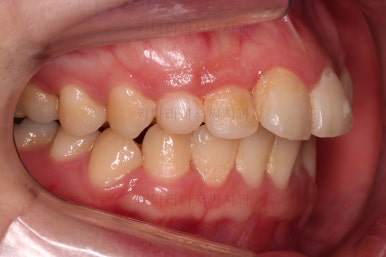

1. 초진

초진 시 입안의 모습입니다.

앞니쪽이 조금 삐뚤어 보인다는 점 이외에는 큰 문제점이 보이지 않죠?

어금니쪽을 자세히 관찰해 보면, 위아래 어금니의 맞물림(교합)이 어긋나 있는데요.

톱니바퀴처럼 물려야 되는 교합이 한 칸 씩 윗니가 아랫니보다 앞으로 나가있는 앵글씨 2급 부정교합 상태였습니다.